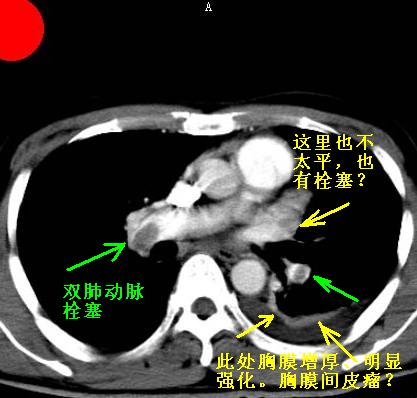

以下是引用jiangjing在2007-1-24 23:35:00的发言:[br]支持 增强扫描见右肺动脉干、左下肺动脉见充盈缺损。印象为:1、右肺动脉干、左下肺动脉栓塞。 2、左侧胸腔积液合并左肺下叶被动性肺不张。

以下是引用rjg199343在2007-1-24 23:22:00的发言:[br]增强扫描见右肺动脉干、左下肺动脉见充盈缺损。印象为:1、右肺动脉干、左下肺动脉栓塞。 2、左侧胸腔积液合并左肺下叶被动性肺不张。

以下是引用影象王在2007-1-25 10:16:00的发言:[br]肺栓塞。确实典型!